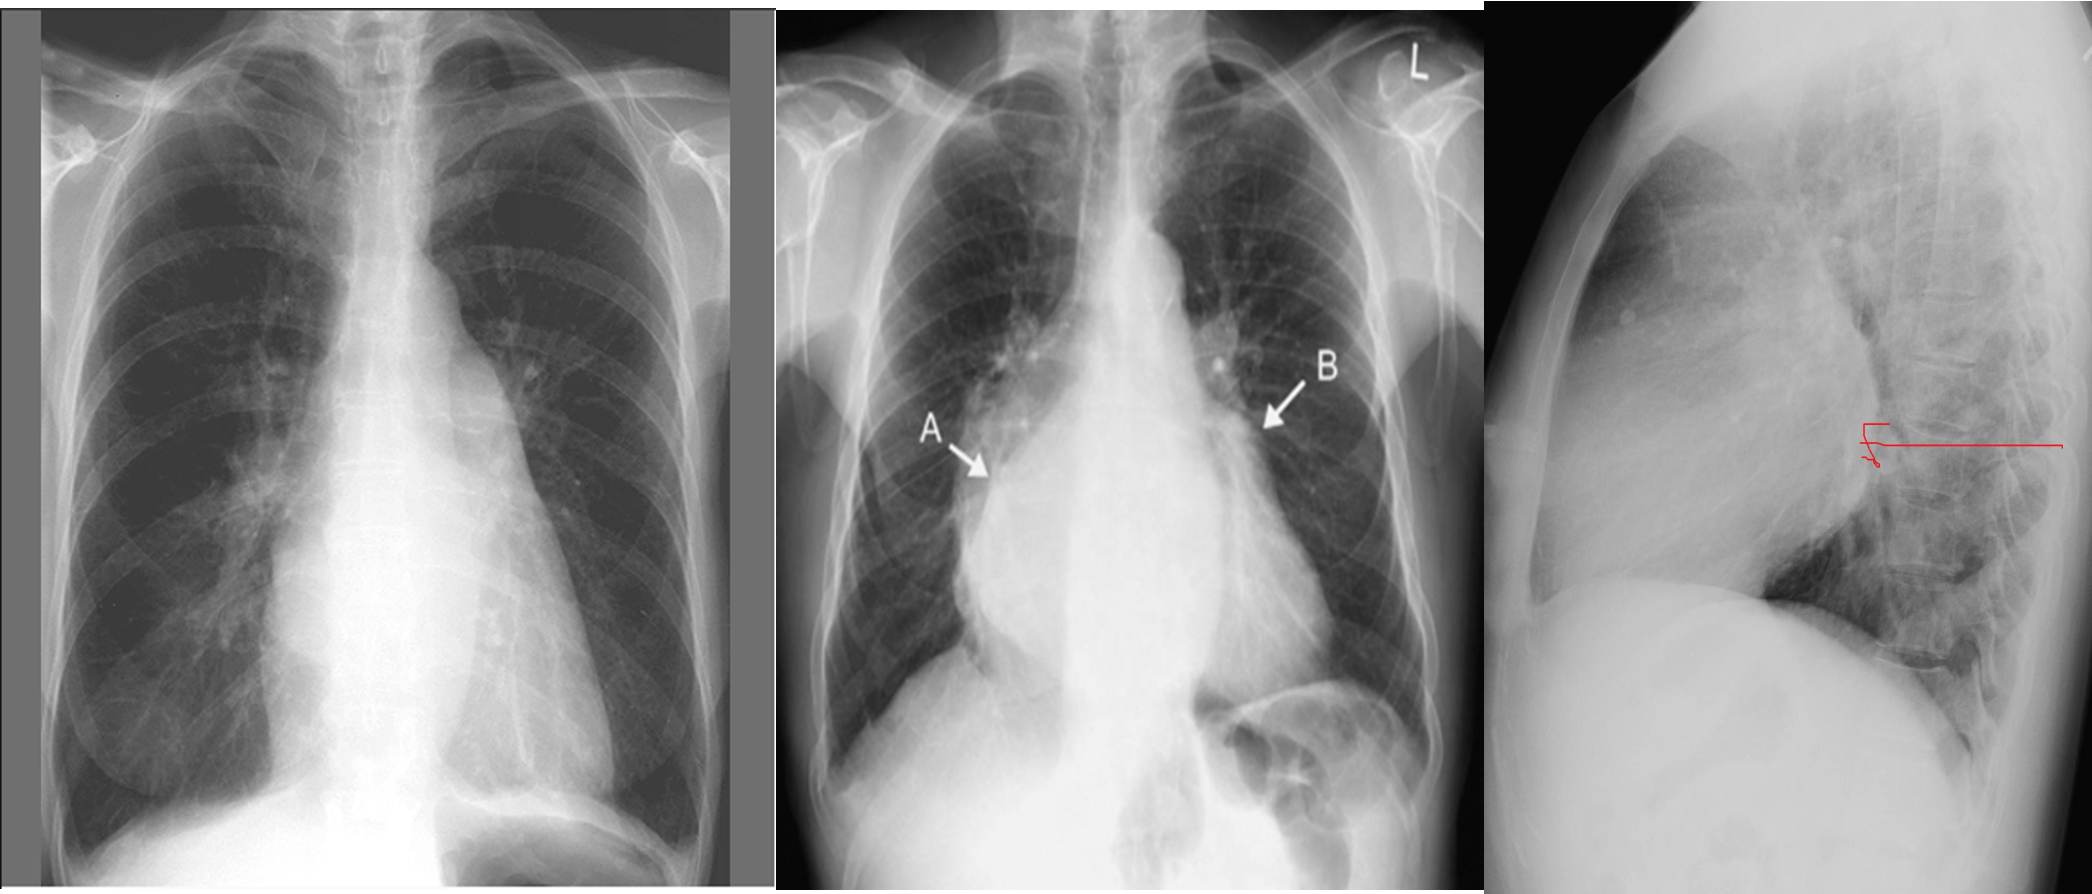

CXR Z

-

Left atrial enlargement

Mitralisation of heart: straightening of left heart border

Elevation of left mainstem bronchus

Evidence of mitral calcification

Evidence of pulmonary edema kerley’s b lines

Double contour of the right border of heart

Complication of mitral stenosis

Imaging

PA view: ⇒ Left atrial enlargement:

- Convexity or straightening of the left atrial appendage.

- Left heart border is straight or convex

- Double density of RTÂ cardiac border

- Elevation of the left main bronchus and splaying of the carina

LA view: posterior protrusion of the upper part of posterior heart border.